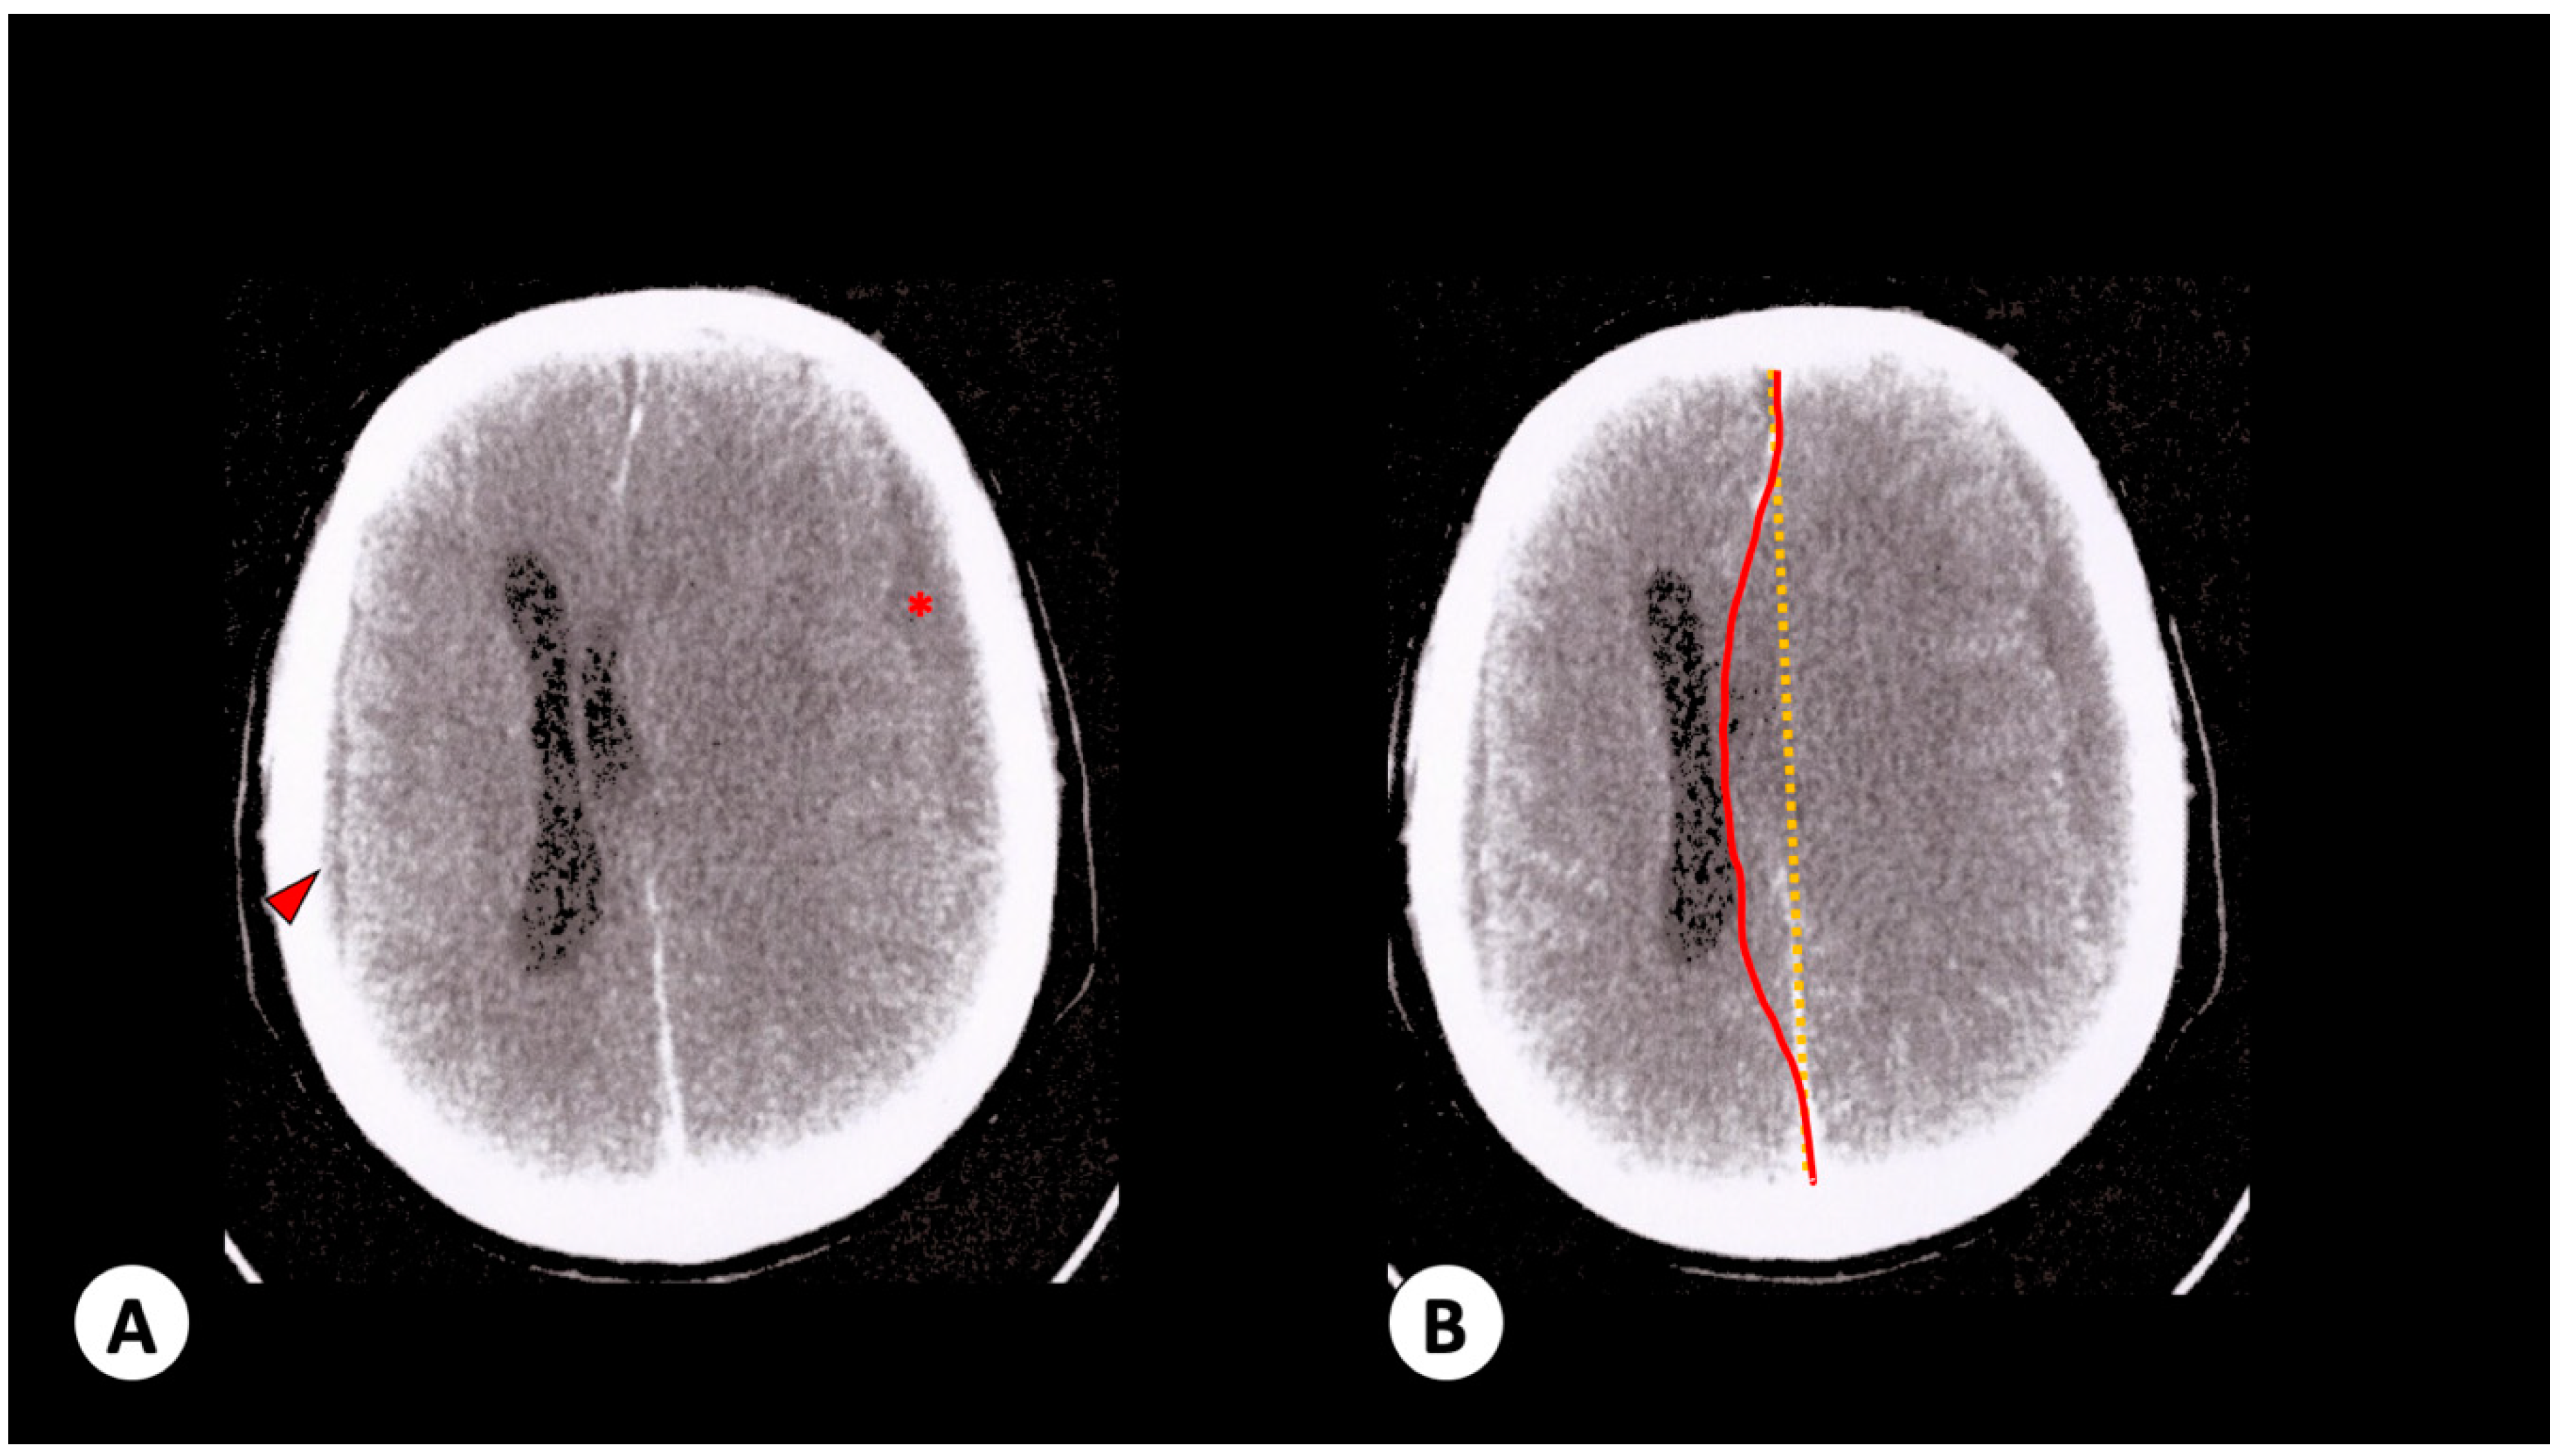

3.1. Case 1

3.2. Case 2

3.3. Case 3